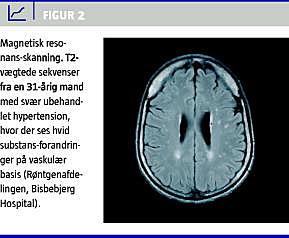

Hypertension medfører en acceleration i udviklingen af aldersinducerede forandringer i hjernens hvide substans, såkaldt leukoaraiose [2]. Disse forandringer kan ses på computertomografi (CT) og magnetiske resonans-skanninger (Figur 1 og Figur 2 ). Forandringerne er af iskæmisk natur og skyldes hypoperfusion i mindre kar, der medfører en udtynding af vævet. Hjernen er yderst følsom for øgning i blodtryksniveauet, og selv få mmHg's øgning i blodtryksniveauet i en døgnblodtryksmåling kan relateres til øget forekomst af hvid substansforandringer og øget hjerneatrofi efter bare få års observationstid [3]. Ud over alder og hypertension bidrager lakunære infarkter, rygning og hyperkolestrolæmi til udvikling af hvid substans-forandringer, idet disse faktorer også fører til iskæmisk cerebrovaskulær sygdom. Personer med hvid substans-forandringer har en øget risiko både for at få apopleksi og udvikle demens.